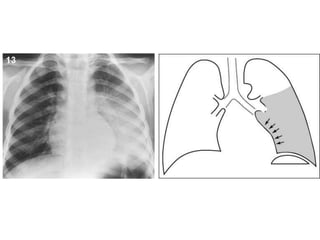

neumotorax

hidroneumotorax